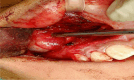

Figures